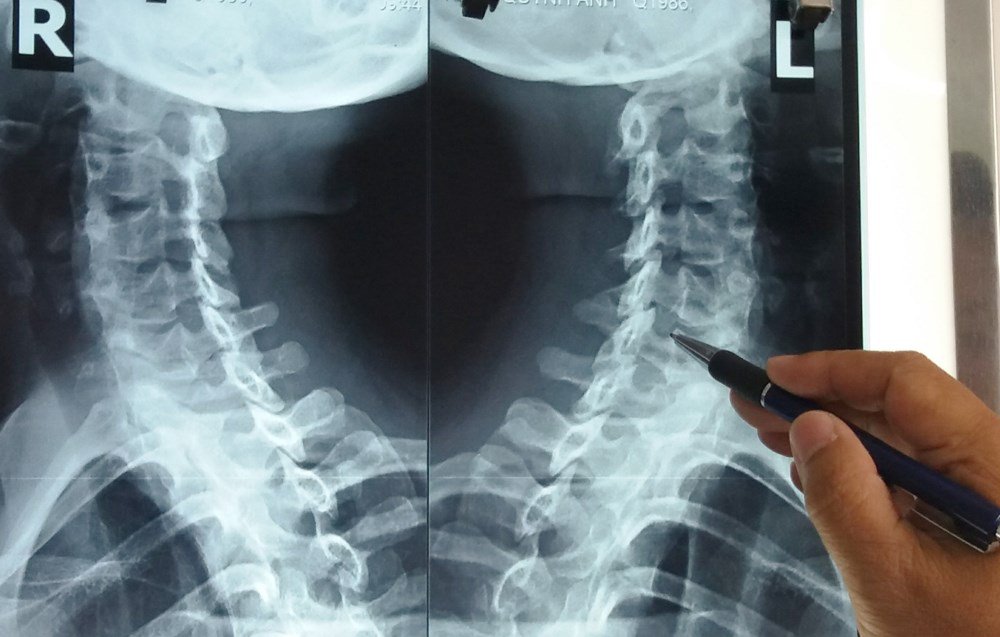

Hình ảnh X-quang nhận diện thoái hóa cột sống cổ.

Biến chứng đáng ngại nhất của thoái hóa cột sống cổ chính là thoát vị đĩa đệm đốt sống cổ. Khi gặp phải biến chứng này thì việc điều trị không đơn giản chút nào vì có thể gây chèn ép tủy sống, thậm chí gây bại liệt một hoặc hai tay, rối loạn cảm giác tứ chi, rối loạn thực vật, chèn ép rễ thần kinh, tủy hoặc gây rối loạn thần kinh thực vật (đại tiểu tiện không tự chủ). Do vậy, để xác định thoái hóa đốt sống cổ cần khám lâm sàng (chuyên khoa thần kinh là tốt nhất), chụp X-quang cột sống cổ, chụp cắt lớp vi tính (CT), tốt nhất là chụp cộng hưởng từ (MRI), kết hợp với các phương pháp thăm dò hiện đại khác để phát hiện, xử lý kịp thời.